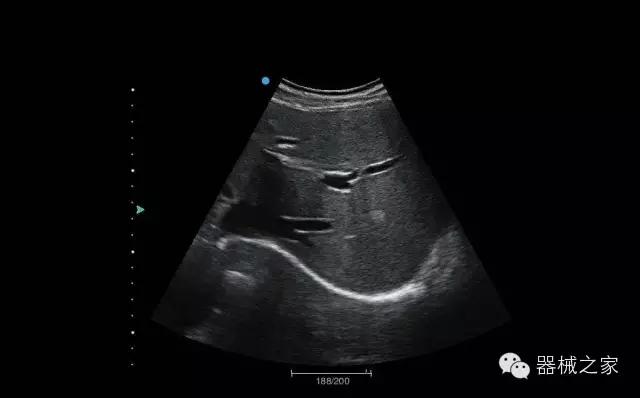

临床图片赏析

产品特点

·装载有采用Multi-Core多核处理的非嵌入式平台,成像效率大大提高,并且能够给用户带来高速、多任务并行信号处理体验;

·优秀的图像效果、强大的功能体验、丰富的探头选择、合理的便携式设计,全中文显示及病人管理界面,使得M7在任何场合、任何时候都能快速响应更好的心血管、腹部、妇产、小器官等常规超声检查以及肌骨、神经、颅脑、术中等新兴领域的使用需求;